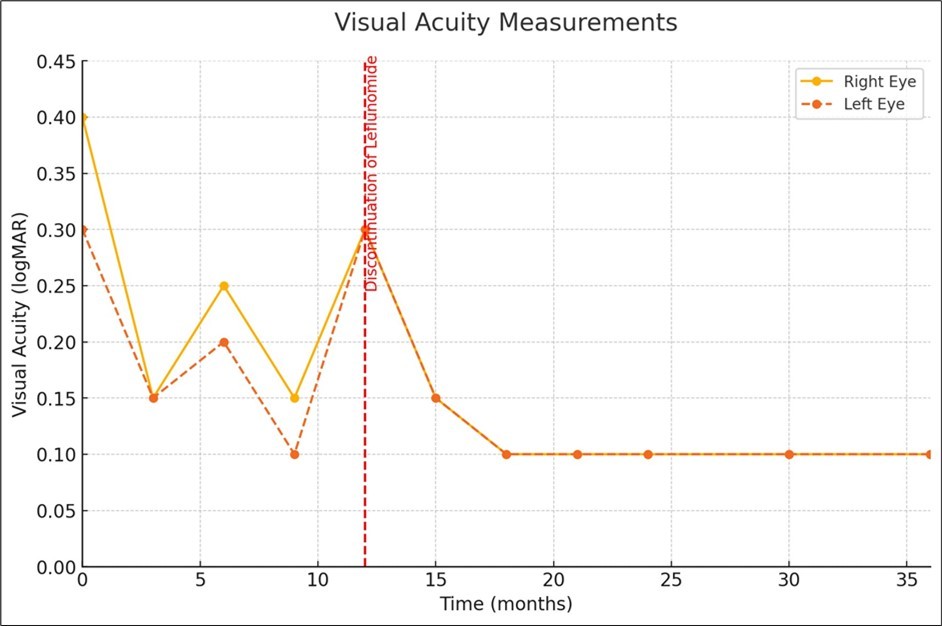

Despite ongoing treatment with topical non-steroidal anti-inflammatory drugs, a carbonic anhydrase inhibitor, and corticosteroids, her VA initially improved, but CME continuously recurred upon discontinuation of the therapy. The patient experienced recurrent CME over the course of one year (Figure 2).

Figure 2.Visual acuity (logMAR) measurements before and after discontinuation of Leflunomide.

Notably, the patient had been undergoing Leflunomide therapy for the entire duration of CME remission and relapse, as indicated by the fluctuations in CFT and VA (Figure 2 and Figure 3). Drug-induced CME from other medications was considered, but the temporal association with Leflunomide use and the absence of other known offending drugs supported Leflunomide as the likely cause. Given the history of Leflunomide use and the clinical findings, a multidisciplinary approach was adopted. The Rheumatology department was consulted to discuss the potential link between Leflunomide and CME. Based on their input and a comprehensive literature review, and considering the findings of a previously reported case of bilateral Leflunomide-induced CME, it was decided to empirically discontinue the drug. 3 The resolution of CME upon discontinuation of Leflunomide further substantiated this diagnosis.